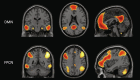

Proteinopathies are key elements in the pathogenesis of age-related neurodegenerative diseases, particularly Alzheimer's disease (AD), with the nature and location of the proteinopathy characterizing much of the disease phenotype. Susceptibility of brain regions to pathology may partly be determined by intrinsic network structure and connectivity. It remains unknown, however, how these networks inform the disease cascade in the context of AD biomarkers, such as beta-amyloid (Aβ), in clinically-normal older adults.The default-mode network (DMN), a prominent intrinsic network, is heavily implicated in AD due to its spatial overlap with AD atrophy patterns and tau deposition. We investigated the influence of baseline Aβ positron emission tomography (PET) signal and intrinsic DMN connectivity on DMN-specific cortical thinning in 120 clinically-normal older adults from the Harvard Aging Brain Study (73 ± 6 years, 58% Female, CDR = 0). Participants underwent11C Pittsburgh Compound-B (PiB) PET, 18F flortaucipir (FTP) PET, and resting-state MRI scans at baselineand longitudinal MRI (3.6 ± 0.96 scans; 5.04 ± 0.8 years). Linear mixed models tested relationships between baseline PiB and DMN connectivity on cortical thinning in a composite of DMN regions. Lower DMN connectivity was associated with faster cortical thinning, but only in those with elevated baseline PiB-PET signal. This relationship was network specific, in that the frontoparietal control network did not account for the observed association. Additionally, the relationship was independent of inferior temporal lobe FTP-PET signal. Our findings provide evidence that compromised DMN connectivity, in the context of preclinical AD, foreshadows neurodegeneration in DMN regions.